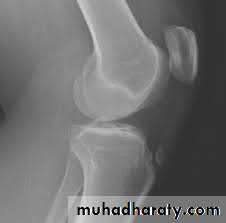

Supracondylar fractures of the femur

Typically the fracture occurs just proximally to the point where the medial and lateral cortices of the femur flare out to form condyles. In young it follow sever trauma and in old follow osteoporosis.A vertical extension of the fracture may split the two condyles apart in a T – shaped fracture line, and sometime there is more extensive comminuation.

Clinically :

pain and deformity in lower thigh after trauma.Knee is swollen and distal pulses should be palpated.

It may injured the popliteal artery and nerves.